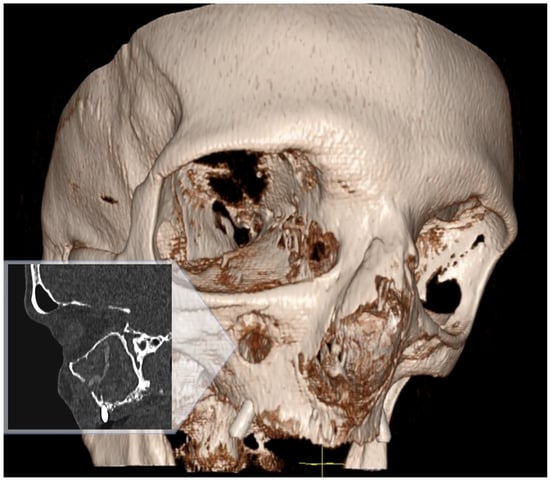

Multi-slice computed tomography (MSCT) revealed mucosal hyperplasia, total opacification of the right maxillary sinus and a solid foreign body within the maxillary sinus. The foreign body had a vermicular narrow shape with an approximate length of ~28 mm. Furthermore, a small perforation of the maxillary sinus anterior wall was observed on MSCT (Figure 1).

Figure 1. MSCT sagittal view and 3D facial bone view both show a perforation of the right maxillary sinus anterior wall, total opacification of the sinus and a foreign body inside.